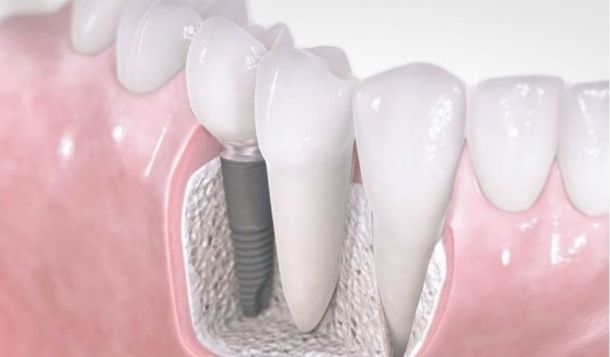

Regeneración ósea del maxilar

En los casos que el paciente dispone de poco hueso para poder colocarle implantes, es necesario aplicar unas técnicas quirúrgicas de regeneración ósea previa a la colocación de los mismos. De este modo los pacientes podrán llevar dientes fijos incluso en situaciones en las que se ha perdido gran cantidad de masa ósea.  Utilizamos materiales bioconductores que nos permiten regenerar hueso de manera fiable y poco agresiva.